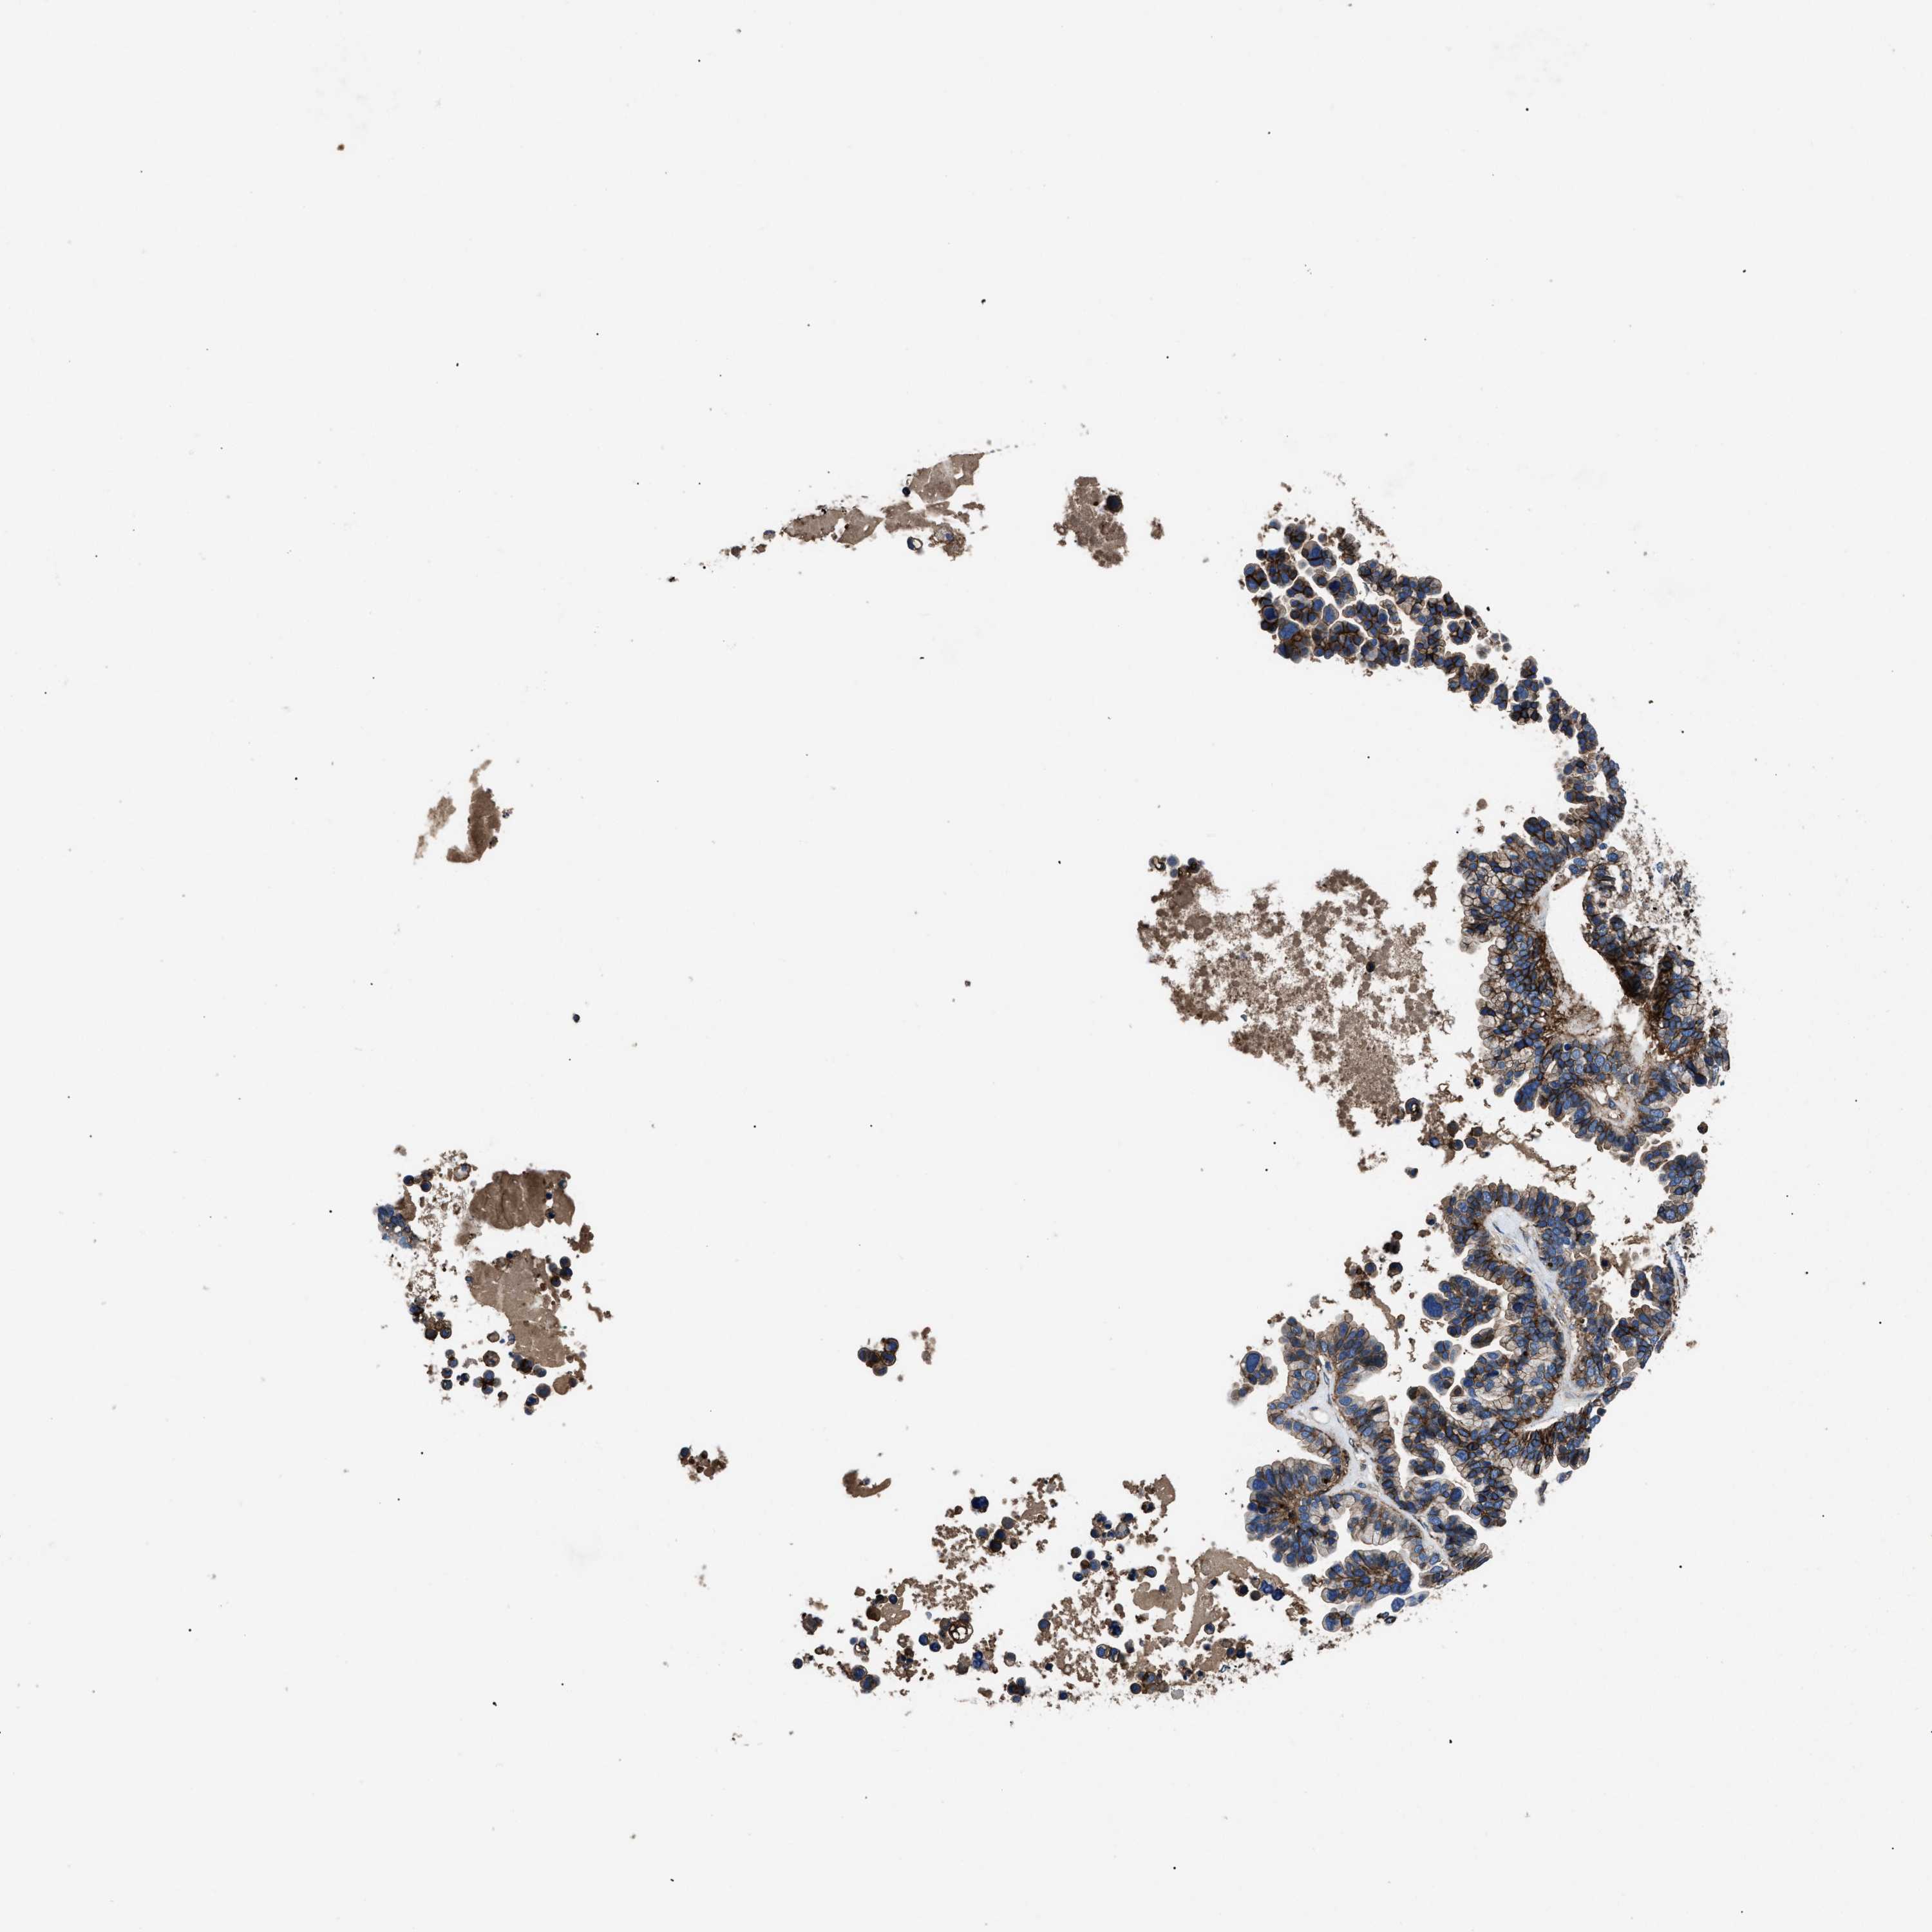

OVARIAN CANCER - Protein expressioni

A mouse-over function shows sample information and annotation data. Click on an image to view it in a full screen mode. Samples can be filtered based on level of antibody staining by selecting one or several of the following categories: high, medium, low and not detected. The assay and annotation is described here.

Note that samples used for immunohistochemistry by the Human Protein Atlas do not correspond to samples in the TCGA dataset.

Antibody stainingi

Antibody staining in the annotated cell types in the current human tissue is reported as not detected, low, medium, or high, based on conventional immunohistochemistry profiling in selected tissues. This score is based on the combination of the staining intensity and fraction of stained cells.

Each image is clickable and will lead to virtual microscopy that enables deeper exploration of all samples and also displays staining intensity scores, fraction scores and subcellular localization as well as patient and tissue information for each sample.

Antibody HPA009285

Antibody HPA017139

Antibody CAB017826

Cystadenocarcinoma, serous, NOS

Carcinoma, endometroid

Cystadenocarcinoma, mucinous, NOS

Carcinoma, NOS